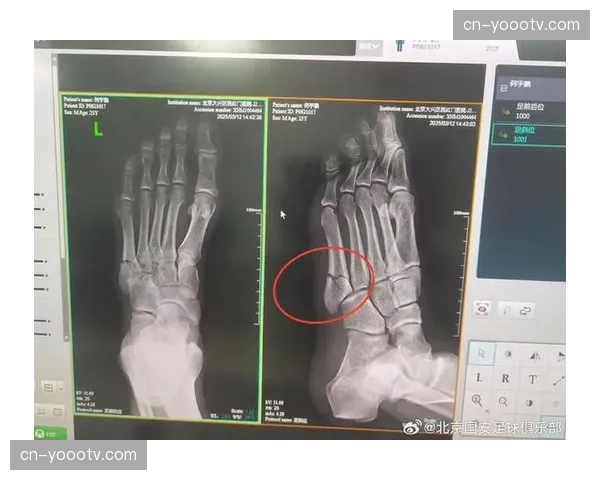

何宇鹏的伤病成为中超2026赛季4月的一大焦点。在近期的训练中,这位大连人队的主力右后卫不幸遭遇跖骨骨折,初步诊断显示康复周期较长。这一突发情况不仅让球队在右路防守上面临深度不足的问题,也对大连人队的...